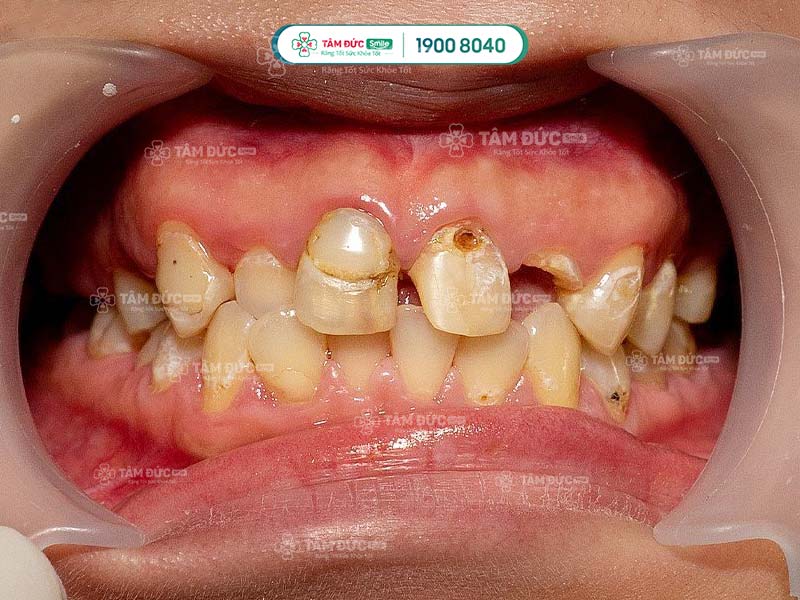

1.1. Sâu răng

Sâu răng là bệnh lý răng miệng phổ biến, có thể dẫn đến mất răng vĩnh viễn. Ở giai đoạn đầu, vết sâu chỉ nhỏ như đầu kim. Nếu Quý khách không chữa trị sâu răng sớm, vết sâu sẽ lan rộng và ăn vào các lớp tổ chức cứng của răng, dẫn đến mẻ vỡ thân răng.

còn chân răng có bọc răng sứ được không

Chấn thương ở răng làm gãy chân răng